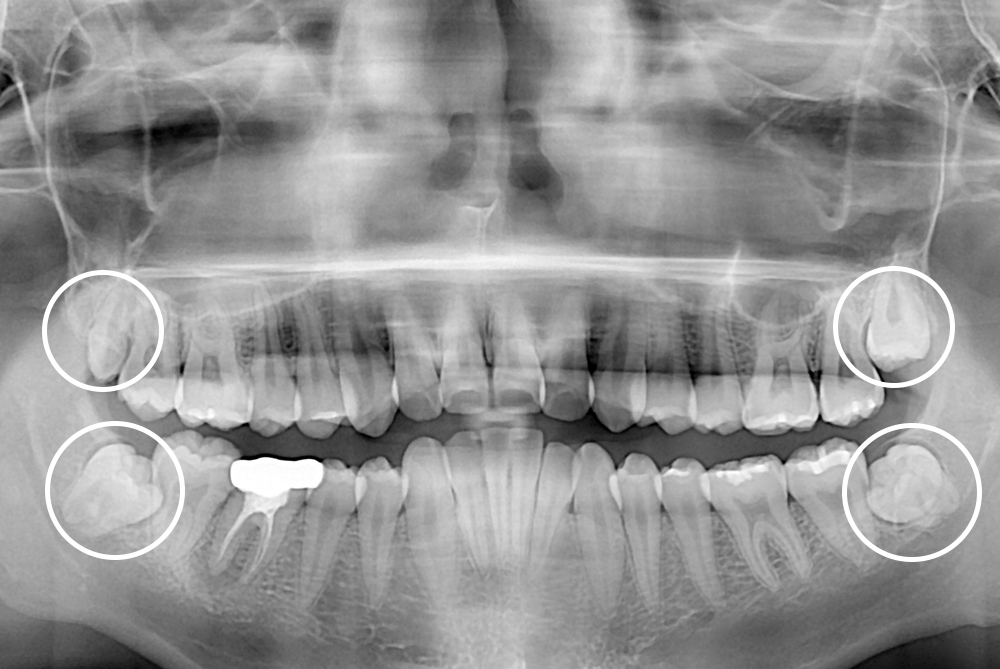

[사랑니] 매복 사랑니 발치

치료후 : 2020-07-14

세종치과는 구강악안면외과학 박사이신 원장님이 발치하는 치과입니다.